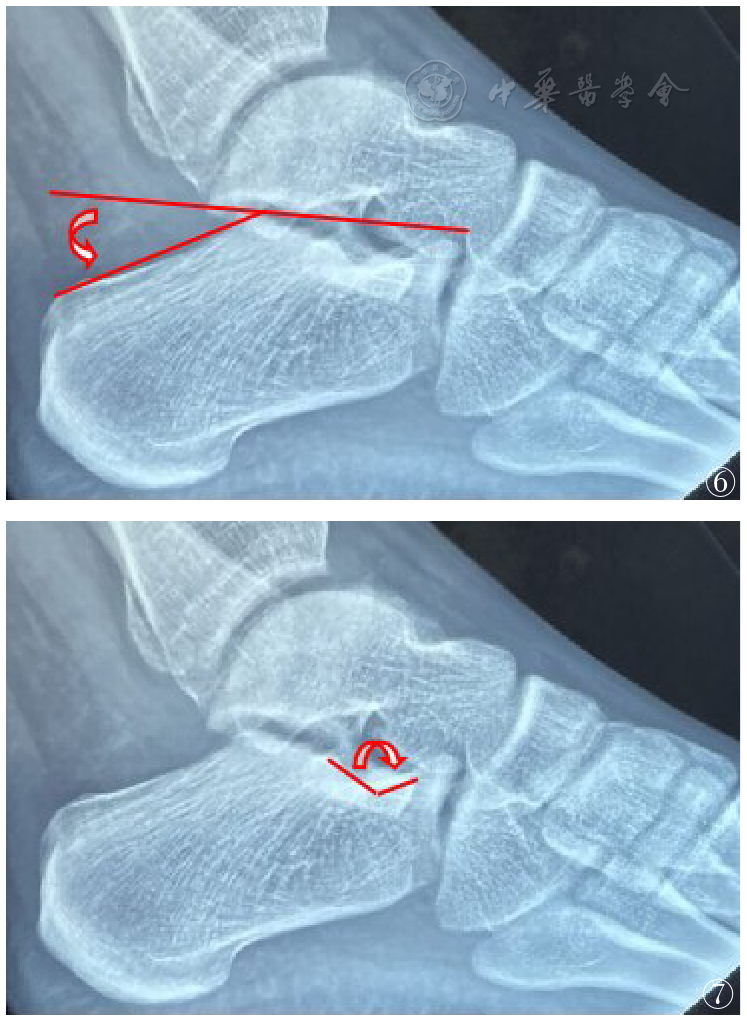

图5 Sanders C亚型

图7 Gissan角